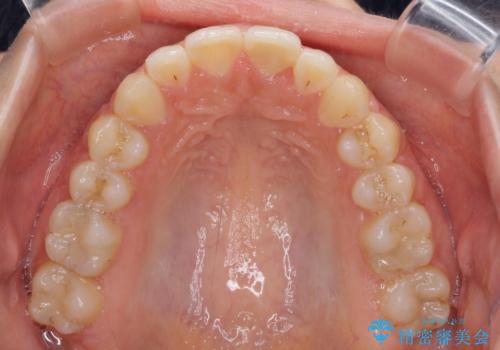

【モニター】オープンバイトをインビザラインで矯正治療

- 前歯の上下スペースによる食べにくさを気にして来院された患者様です。

インビザラインにより上下の前歯の隙間を閉じていくこととしました。

前歯のデコボコの解消と並行して上下の奥歯を圧下させるようにすることで、前歯を接触させるように計画しました。

上下の隙間に舌が入り込むことがオープンバイトの原因であったため、舌の筋肉のトレーニングも並行して行い、後戻りの抑制を図りました。